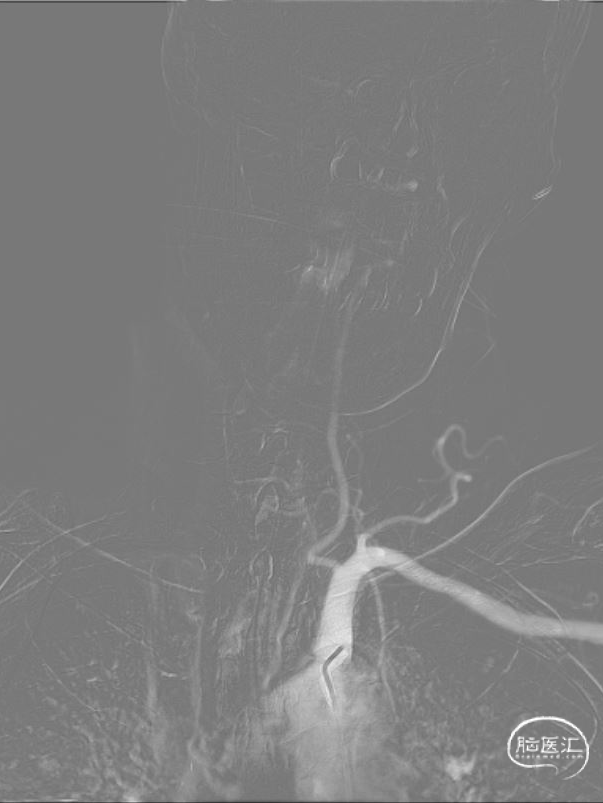

双侧椎动脉造影,右侧椎动脉V3段中度狭窄,基底动脉闭塞。

因右侧椎动脉颅内段血管狭窄,选取左侧椎动脉入路。左侧椎动脉开口迂曲,6F 导引导管放置于左侧椎动脉V2段。

200cm微导丝引导微导管通过闭塞段,微导管造影确认血管位于真腔。

采用交换技术将300cm微导丝放置于左侧大脑后动脉P1段,采用颅内球囊扩张导管 1.75*12mm 缓慢扩张至命名压6atm,扩张后路图提示基底动脉显影,基底动脉近端重度狭窄。

基底动脉远端双侧大脑后动脉纤细,血管迂曲,为减少器械交换造成医源性损伤。且球囊扩张后直接释放支架,选用21系列 Fastunnel®输送型球囊扩张导管 2.5*15mm压力泵缓慢扩张至命名压6atm。

经21系列 Fastunnel®输送型球囊扩张导管 2.5*15mm定位自膨式闭环支架 4.5*22mm(No Tip)。

经21系列 Fastunnel®输送型球囊扩张导管 2.5*15mm释放自膨式闭环支架后狭窄改善,双侧大脑后动脉、双侧小脑上动脉血管显影增强。

左侧椎动脉正侧位造影显示基底动脉显影狭窄改善。